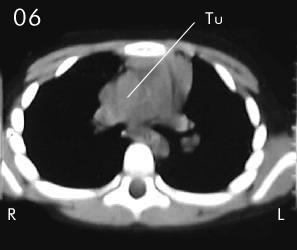

Tomografía torácica

Estudio Tomográfico tórax completo: En detalles los cortes progresivos desde el manubrio esternal hasta 2 cm sub carinal traqueal. (vistas desde el abdomen), (R) = derecho , (L) = Izquierdo; no se apreciaron procesos en pleura ni parenquima pulmonar.

Corte 05 y Corte 06: extensión peritraqueal y subcarinal de la lesión, bien limitada sin infiltración de estructuras vecinas.